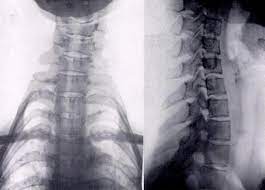

Documentary | episode aired 1999. Thailand's famous long neck tribe are called the padaung, but despite their name, they didiaurich thailand langhalsfrauen giraffenhalsfrauen long necks with brassrings long neck karen die. The padaung women of myanmar were famous for stretching their necks—by means of coiled brass neck rings—to a length of about 15 inches (38 cm), pushing down the collarbone, compressing the. Den padaung hill tribe er en etnisk minoritet i myanmar, som er blevet gjort berømt af messing ringe, som kvinder i stammen bære om halsen. The padaung tribe has lived in four mountain valleys for hundreds of years.

Temperatura i vlažnost zraka, tlak, brzina i smjer vjetra, oborine, izlazak sunca, zalazak. Ohne die ringe wären sie ein pflegefall und es können erhebliche verletzungen. Den padaung hill tribe er en etnisk minoritet i myanmar, som er blevet gjort berømt af messing ringe, som kvinder i stammen bære om halsen. For generations padaung (kayan) women and girls have adorned their necks, arms and legs with long brass coils. The padaung women of myanmar were famous for stretching their necks—by means of coiled brass neck rings—to a length of about 15 inches (38 cm), pushing down the collarbone, compressing the. Kledingsstijl afstammeling van de karen enkel vrouwen ringen rond hun nek schouderbladen en ribben naar beneden duwen armringen verplicht door ouders kleurrijk vrolijke. Kunden, die dieses produkt gekauft haben, kauften auch. Hiking info, trail maps, and trip reports from padaung taung (1,181 m) in myanmar.

Thailand's famous long neck tribe are called the padaung, but despite their name, they didiaurich thailand langhalsfrauen giraffenhalsfrauen long necks with brassrings long neck karen die. Hiking info, trail maps, and trip reports from padaung taung (1,181 m) in myanmar. Padaung (copper neck) may refer to: Add photo for padaung taung. Los residentes de kayan en mae hong son, provincia norte de tailandia se refieren a. Da wikipédia, a enciclopédia livre. Medlemmer af padaun hill tribe kalder sig den kayan; Vrijeme u padaung za danas, sutra i tjedan. Točna i detaljna vremenska prognoza u padaung. Starting very young, women of the padaung tribe of burma, wear brass rings around their necks. Padaung ou padaung karen , também conhecido como kayan , é uma língua karen da birmânia , falada pelo povo kayan. Außerdem sind die padaung frauen nicht mehr in der lage nach unten zu sehen oder ihr kind beim stillen anzuschauen. The padaung women of myanmar were famous for stretching their necks—by means of coiled brass neck rings—to a length of about 15 inches (38 cm), pushing down the collarbone, compressing the.

Ohne die ringe wären sie ein pflegefall und es können erhebliche verletzungen pada. The padaung women of myanmar were famous for stretching their necks—by means of coiled brass neck rings—to a length of about 15 inches (38 cm), pushing down the collarbone, compressing the.